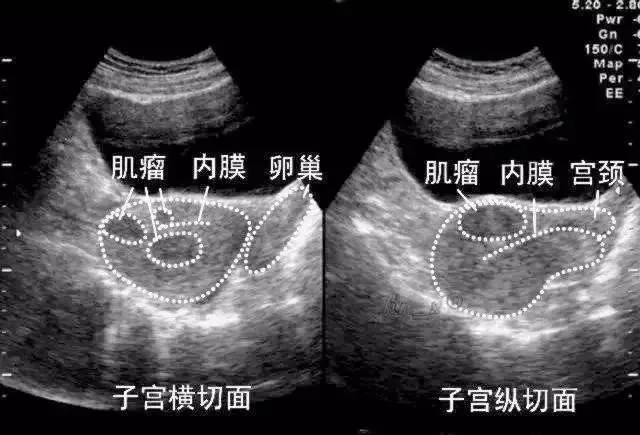

子宫肌瘤

●子宫肌瘤:是女性生殖器中最常见的良性肿瘤。肌瘤一般为实质性圆形结节,表面光滑,呈白色,质硬,切面为旋涡状结构,周围肌组织受压形成假包膜,包膜中分布有放射状血管,供给肌瘤营养,肌瘤越大,血管越多越粗。

●二维超声表现:子宫增大、形态失常,肌壁间肌瘤和粘膜下肌瘤子宫常均匀增大;浆膜下肌瘤、较大或数目较多的肌壁间肌瘤常导致子宫不规则增大

肌壁间肌瘤

子宫肌层内异常回声结节,多呈低回声,较大的肌瘤伴后方回声衰减,瘤体与宫壁正常肌层之间界限较清晰。